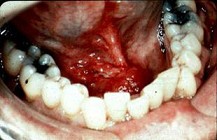

2.男,40歲,發(fā)現(xiàn)右側(cè)口底部有一核桃大小質(zhì)硬腫塊(如圖),觸診浸潤已過中線。右側(cè)頜下可捫及2個腫大淋巴結(jié),黏連;左側(cè)未捫及明顯腫大淋巴結(jié)。關(guān)于頸部淋巴結(jié)的處理,以下哪項最佳  (    )

正確答案:C